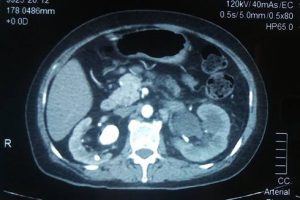

BVXA VĨNH LONG – XỬ TRÍ THÀNH CÔNG BỆNH NHÂN SỎI THẬN, SỎI NIỆU QUẢN TRÁI CÓ NGUY CƠ SỐC NHIỄM TRÙNG

Bệnh nhân bị sỏi thận, sỏi niệu quản trái có nguy cơ sốc nhiễm trùng đã được các bác sĩ Bệnh viện Đa khoa Xuyên Á – Vĩnh Long kịp thời đặt 2 ống thông JJ qua vị trí sỏi gây tắc nghẽn để dẫn lưu mủ màu trắng đục. Rất nhanh sau đó, bệnh nhân giảm đau hông lưng 2 bên, hết sốt, sinh hiệu ổn.